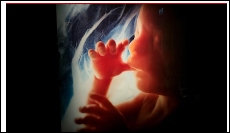

Air pollution particles found in mothers’ placentas

Scientists have found the first evidence that particles of air pollution travel through pregnant women’s lungs and lodge in their placentas. Toxic air is already strongly linked to harm in foetuses but how the damage is done is unknown. The new study, involving mothers living in London, UK, revealed sooty particles in the placentas of each of their babies and researchers say it is quite possible the particles entered the foetuses too.

“It is a worrying problem – there is a massive association between air pollution a mother breathes in and the effect it has on the foetus,” said Dr Lisa Miyashita, at Queen Mary University of London, one of the research team. “It is always good if possible to take less polluted routes if you are pregnant – or indeed if you are not pregnant. I avoid busy roads when I walk to the station.”

A series of previous studies have shown that air pollution significantly increases the risk of premature birth and of low birth weight, leading to lifelong damage to health. A large study of more than 500,000 births in London, published in December, confirmed the link and led doctors to say that the implications for many millions of women in polluted cities around the world are “something approaching a public health catastrophe”.(theguardian)…[+]